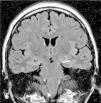

Los hallazgos en las IRM se pueden observar en las figuras 1–8. Se observa predominancia en el diagnóstico de esclerosis del hipocampo en los pacientes con epilepsia temporal, tanto en el grupo de enfermos respondedores como no respondedores. En la epilepsia extratemporal se observa con mayor frecuencia la presencia de malformaciones del desarrollo cortical y/o tumores, que fueron consideradas en el mismo grupo debido a que estas lesiones muchas veces resultan indistinguibles unas de otras a través de las IRM. Esta predominancia se observa más acentuada en el grupo de enfermos resistentes al tratamiento.